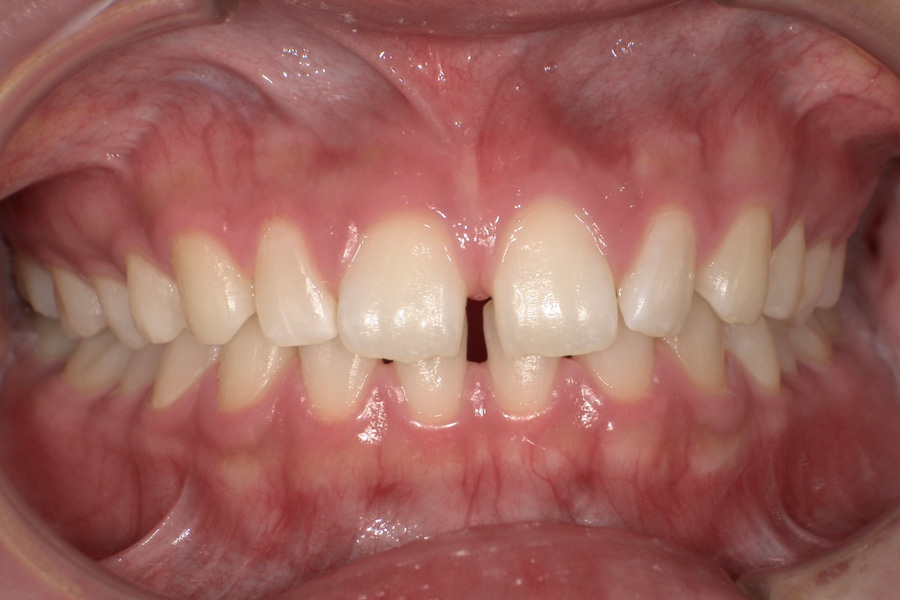

虫歯があるから削ったり悪くなったから抜くのではなく、まずは虫歯と歯周病が起きないようにより良い環境づくりをすること、そうすることによって歯を長く維持することが可能となります。

そのためには、健康状態に関する情報と生活習慣などの状況を把握したうえで、お口の中のリスク評価をおこないます。

その結果をもとに、お一人お一人にあった治療計画をご提案させていただきます。